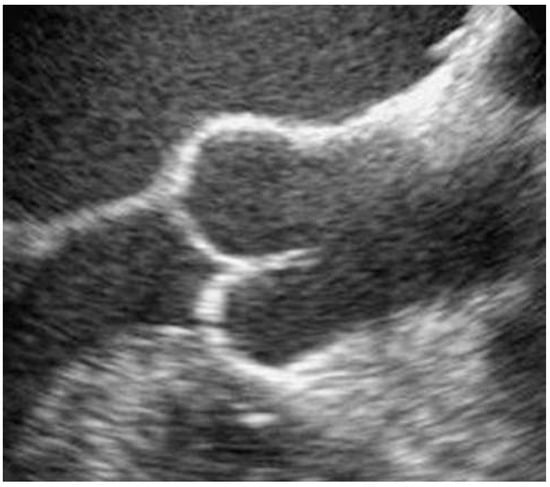

Figure 3. Transösophageale Echokardiographie, Längsschnitt.

Die vier Taschen der QAK unserer Patientin waren symmetrisch konfiguriert, wenig verdickt und gut beweglich. Im Farbdoppler zeigte sich eine leichte zentrale Aorteninsuffizienz am Koaptationspunkt der vier Taschen. Der Hauptstamm der linken Koronararterie zeigte einen orthotopen Abgang. Nebenbefundlich fand sich ein PFO.